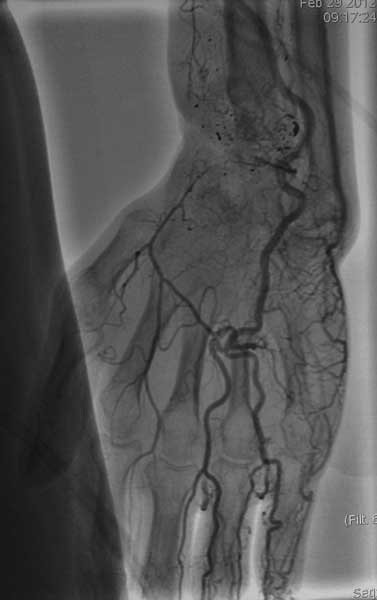

Изучали ли вы достаточно тщательно ангиограммы пораженного сегмента? Если да, то вы обратили внимание, что в артериальной фазе практически полностью отсутствует контрастирование лучевой артерии в зоне дефекта, тем самым вы имеете разорванную артериальную дугу и стабильный кровоток только в одном бассейне-локтевой артерии, тыльная межкостная не контрастировалась. Невзирая на это, вы предлагаете использовать пластику дефекта трансплантатом локтевой кости на сосудистом пучке (единственном, который объективно сохранился). Не боитесь ли вы возникновения проблем кровоснабжения кисти при выполнении данного вмешательства и как вы готовы бороться с этим (имею в виду оснащение, специалистов по микрохирургии и пр.)-это вопрос номер 2.